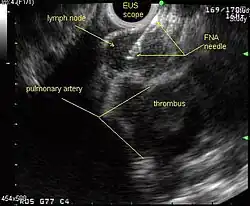

Endobronchial ultrasound (EBUS)

As mentioned in the table, EUS cannot reliably access right sided paratracheal lymph node stations 2R and 4R and may not be optimal for the left sided paratracheal lymph node stations either. An adaptation of the endoscopic ultrasound scope originally designed for the gastrointestinal tract is known as endobronchial ultrasound (EBUS). The instrument is inserted into the trachea rather than the esophagus. There are two types of EBUS bronchoscopes available: radial catheter probe and convex probe EBUS (CP-EBUS),[37] but only the latter concerns us here. Early experience with mediastinal staging by CP-EBUS appears very promising with sensitivities ranging from 92 to 96 percent in 4 series comprising 70 to 502 patients.[38][39][40][41]

Combined ultrasound

Many patients will, if given a choice, prefer an instrument which is inserted into the esophagus (EUS) over one which is inserted into the trachea (EBUS). Furthermore, many patients with suspected lung cancer will have other smoking related illnesses, such as emphysema or COPD, which makes a bronchoscopy-like procedure (EBUS) a higher risk than an upper endoscopy through the esophagus (EUS). An area of active and emerging research concerns the value of combining EUS and EBUS in a single session, one specialist following the other, or -even more convenient- a dual trained operator doing one or the other – or both- as needed.

EUS-FNA and EBUS-FNA are complementary techniques. EUS has the highest yield in the posterior inferior mediastinum, and EBUS is strongest for the superior anterior mediastinum. Some lymph node stations can only be accessed by one method and not the other (for example, station 2 and 4 L and 3 are hard or impossible to see by EUS, stations 5 and 8 cannot be biopsied by EBUS). Together, EBUS and EUS cover the entire mediastinum (except possibly station 6) and complete mediastinal staging should be possible with a combination of these two procedures. This combination could conceptually eliminate the need for most surgical mediastinoscopies and in fact be more comprehensive.

When combined, this approach has been termed "complete medical mediastinoscopy." EUS-FNA with EBUS may allow near-complete, minimally invasive mediastinal staging in patients with suspected lung cancer [42]